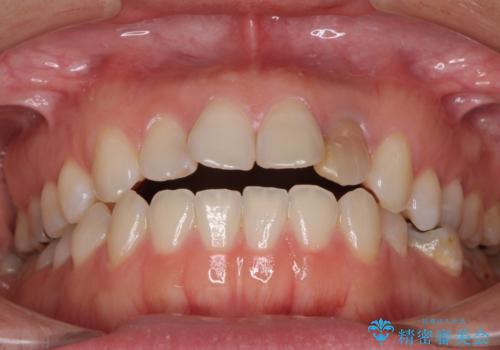

開咬と変色した前歯 インビザライン矯正とオールセラミッククラウン治療

- 前歯の開咬と失活により変色した前歯を気にして来院された患者様です。

開咬の治療は、前歯を閉じるように引っ張り出すよりも、上下臼歯を圧下(骨内にめり込ませる)させることで進める方が長期的に安定した歯列を維持できます。

インビザラインは臼歯の圧下を効果的に行えるため、インビザラインを用いて矯正治療を行うこととしました。

矯正治療が概ね終了した時点で前歯をオールセラミッククラウンにて補綴治療を行い、その後インビザラインにて細かい部分を仕上げていくことしました。

オープンバイトは舌の突出癖により誘発され、治療後も突出癖が残っている容易に後戻りしてしまいます。

治療期間を短縮するためにも、舌突出癖の改善が極めて重要となります。